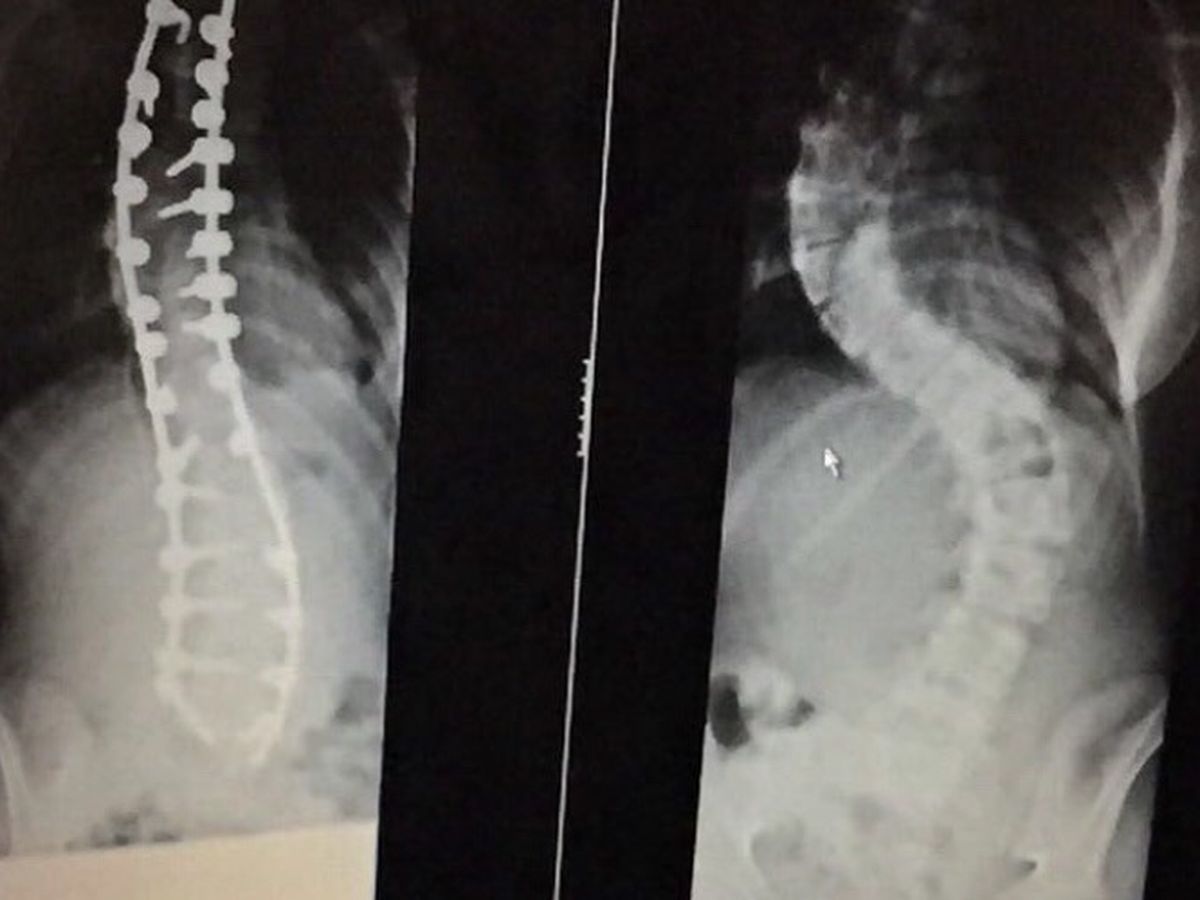

Scoliosis is a condition where the spine abnormally curves. It affects people of all backgrounds,

and it has not yet been discovered what the cause of scoliosis is.

Our organisation specialises in young people who have been surgically treated for Adolescent Idiopathic Scoliosis. Often shorthanded to AIS. This type of scoliosis (AIS) generally appears in tween and teenage years, and is especially common in girls. It is often spotted long after it has developed and doctors do not know what causes it.